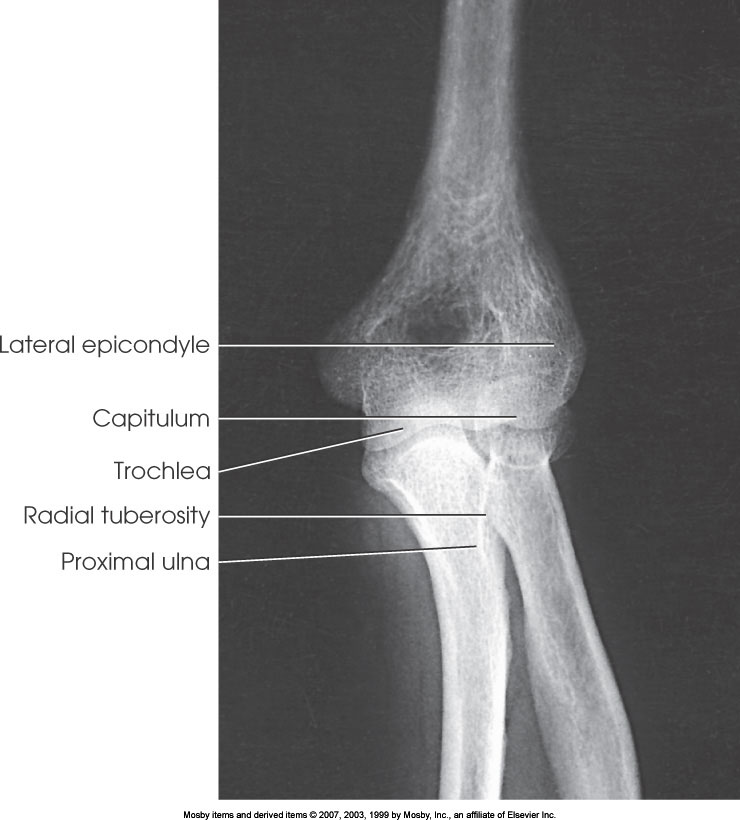

AP Elbow

AP Oblique Elbow (External Rotation)